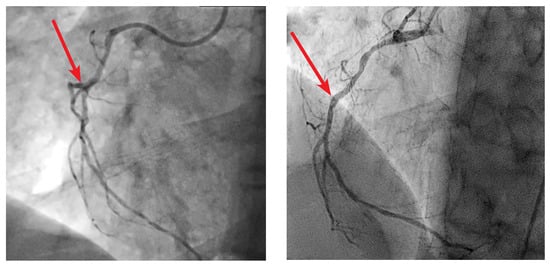

Retrospectively, upon review and comparison of previous angiograms from other hospitals, we could identify a blunt ostial occlusion of one small RVB of the RCA (Figure 5), which matched both with the clinical presentation and the CMR findings.

Figure 5. Comparison of the previous right coronary angiography (left) with the actual examination (right). Retrospectively a missing branch was noted.